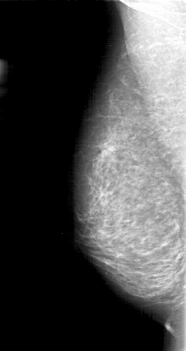

D_4069_1.RIGHT_MLO

LEFT_MLO LINES 4996 PIXELS_PER_LINE 2341 BITS_PER_PIXEL 12 RESOLUTION 43.5 OVERLAY

FILE: D_4069_1.LEFT_MLO.OVERLAY

TOTAL_ABNORMALITIES 1

ABNORMALITY 1

LESION_TYPE MASS SHAPE LOBULATED MARGINS MICROLOBULATED

ASSESSMENT 0

SUBTLETY 3

PATHOLOGY BENIGN

TOTAL_OUTLINES 1

BOUNDARY